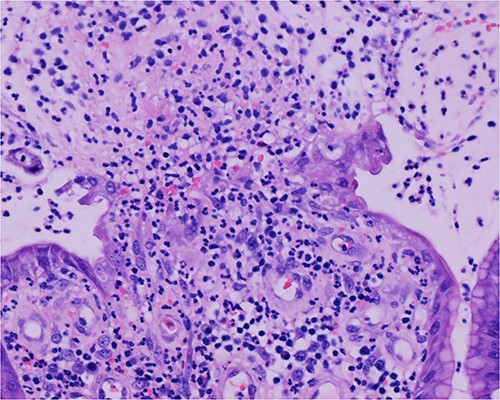

Histologic sections of the polyps demonstrated benign gastric hyperplastic polyps with acute and chronic gastritis (Fig. 2). Portions of the gastric polyps and adjacent mucosa were covered by inflammatory cell exudate (Fig. 3). Higher magnification revealed conspicuous volcanic-like eruption of the exudate, reminiscent of pseudomembranous gastritis (Fig. 4). Alcian yellow and GMS stains were negative for Helicobacter pylori and fungal organisms, respectively.

Biopsy of the gastric polyps is consistent with hyperplastic polyps, focally covered by inflammatory volcanic eruption.